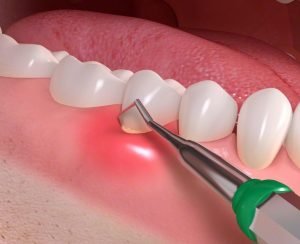

Very specific instruments are used to target each and every surface of the teeth to mechanically release mineral and bacteria above and below the gums. Only when this debris is completely removed can the gum disease reverse or stabilize. Although this falls under a ‘clean’, this procedure requires a high level of skill set, precision and clinical time. The care and technique used makes all the difference in terms of whether or not the gum disease is truly managed. A ‘quick clean’ will only remove stains you can see, but often make no difference to significant underlying gum disease.